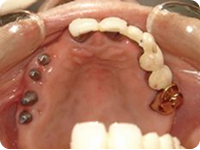

施術例③

治療中

治療途中の写真です。

前歯の部分は骨が無いためインプラントを入れる場合、骨移植などの手術が必要です。

大掛かりな事はせず骨の有る部分にだけ、インプラントを4本埋め込みました。

治療後

固定式のセラミックのブリッジで施術しました。